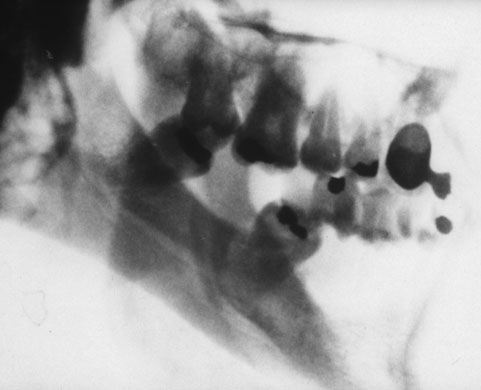

Chad A man left with only two teeth in his lower jaw ­after being t­ortured with an electric t­runcheon. Photograph: Courtesy Hermann Vogel